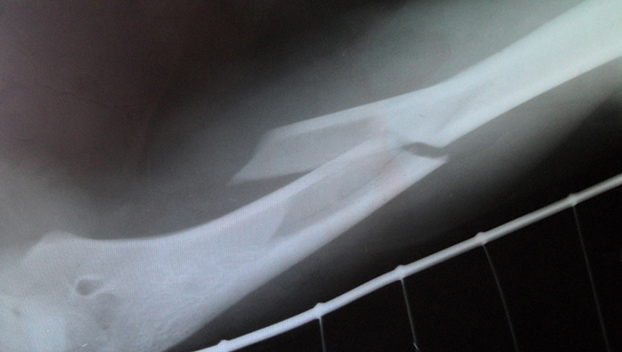

ИзображениеВосьмилетнего Владимира в травматологию привезли родители. Рентген показал перелом правой руки. Близкие и сам ребенок не стали скрывать от врачей правду. Выяснилось, что днем в школе Вова подрался с другим учеником, на четыре года старше. Да и раньше дети нередко конфликтовали друг с другом. На сей раз кулацкий бой между мальчиками завершился для младшего его участника печально.

Кроме перелома руки у ребенка диагностировали гематомы, множество царапин и ссадин. О происшествии травматологи сообщили в полицию. Там классифицировали случившееся как «нанесение телесных повреждений средней тяжести». Но поскольку наказание несовершеннолетнего законом не предусмотрено, решили строго взяться за родителей задиристого школьника. Кроме того, что семью как неблагополучную возьмут на учет, родителей еще привлекут к ответственности за плохое воспитание сына.